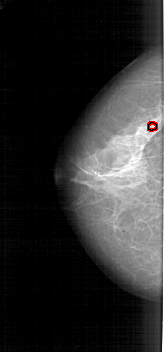

A_1946_1.LEFT_MLO

LEFT_MLO LINES 5491 PIXELS_PER_LINE 2461 BITS_PER_PIXEL 12 RESOLUTION 43.5 OVERLAY

FILE: A_1946_1.LEFT_MLO.OVERLAY

TOTAL_ABNORMALITIES 1

ABNORMALITY 1

LESION_TYPE CALCIFICATION TYPE PLEOMORPHIC DISTRIBUTION CLUSTERED

ASSESSMENT 4

SUBTLETY 3

PATHOLOGY BENIGN

TOTAL_OUTLINES 1

BOUNDARY